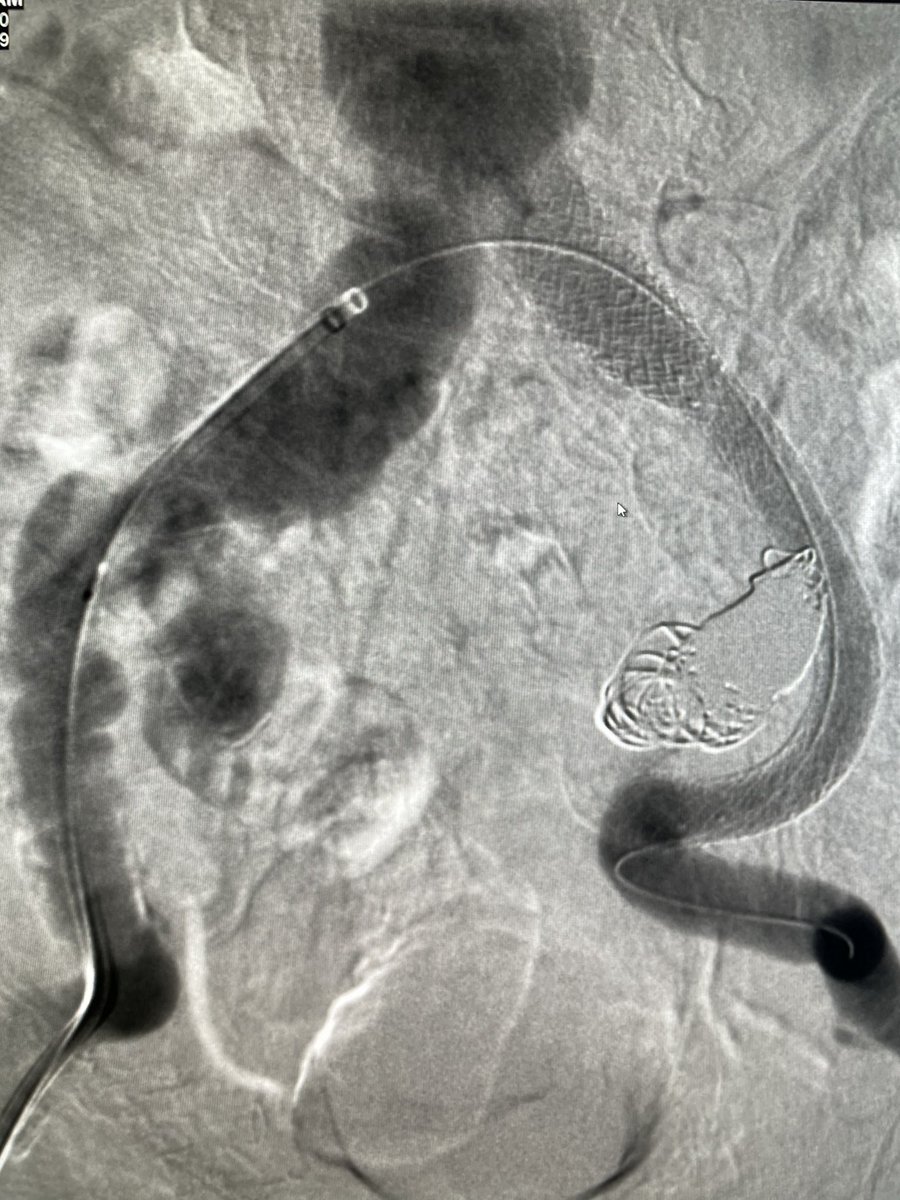

@ChengaziMD @t_intheleadcoat @SDhandMD @drochohan @kmadass @JayMathewsMD @CHICKVIR @Dr_Sudi @DrJayMohan @hkdamonster @SyedYNaqvi1 Nice save with minimal XR, a little IVUS as well? Lucky to have your expertise. I’ve also been preferring IJ when possible